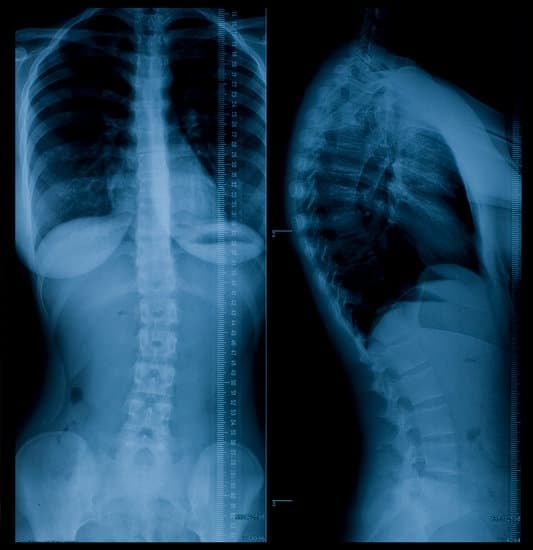

흉요추 골절의 진단

흉요추 골절은 의료 전문가의 평가와 영상 검사를 통해 진단됩니다.

X선 검사: 척추뼈의 골절 여부를 확인할 수 있습니다.